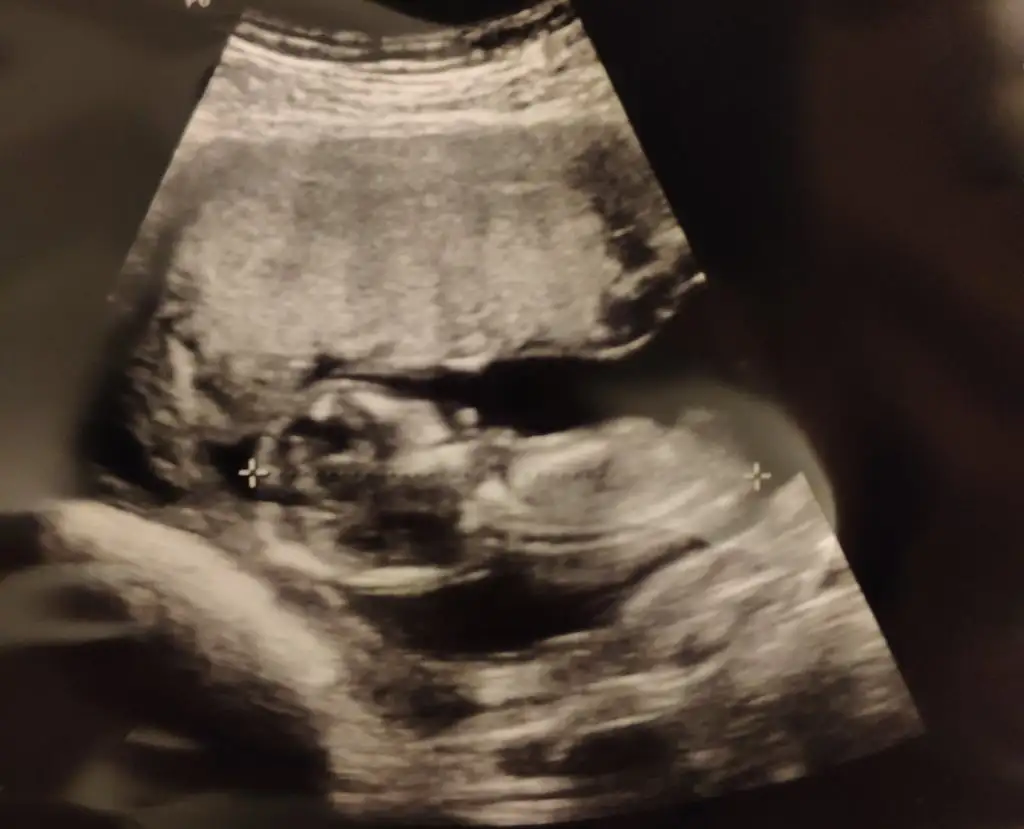

Kızlar cinsiyeti erkek mıdır ?

IMG-20190430-WA0015.webp